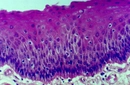

Çiğneme kasları, ağız içinde bulunan ve yiyeceklerin mekanik olarak parçalanarak sindirim sürecine hazırlanmasında önemli rol oynayan kas gruplarıdır. Bu kaslar, yalnızca yiyeceklerin parçalanmasında değil, aynı zamanda konuşma, yutma ve yüz ifadelerinin oluşumunda da kritik bir işlev üstlenmektedir. Çiğneme Kaslarının Anatomik Yapısı Çiğneme kasları, başın yan tarafında yer alan birkaç ana kas grubundan oluşur. Bu kaslar arasında en önemli olanları şunlardır:

Bu kaslar, çiğneme hareketlerini gerçekleştirirken, alt çenenin yukarı, aşağı ve yan hareketlerini sağlamaktadır. Çiğneme Kaslarının Fonksiyonları Çiğneme kasları, aşağıdaki temel fonksiyonları yerine getirir:

Çiğneme Kaslarının Sağlık Üzerindeki Etkileri Çiğneme kaslarının sağlıklı bir şekilde işlev görmesi, genel sağlık açısından oldukça önemlidir. İşlevlerini düzgün bir şekilde yerine getiren çiğneme kasları, aşağıdaki sağlık faydalarını sağlar: